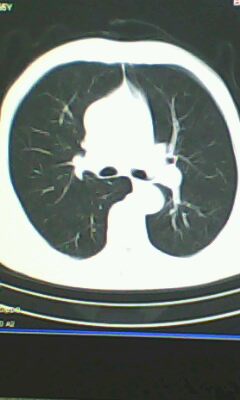

胸廓呈桶状,双膈低平,肺实质及纵隔未见明显异常密度灶考虑肺气肿.

肺气肿

以下是引用ctkz987在2010-5-5 21:30:00的发言:[br]胸廓呈桶状,双膈低平,肺实质及纵隔未见明显异常密度灶考虑肺气肿.

做个肺功能检查。肺ct无明显异常。

弥漫性肺气肿 但内胆管轻度扩张

临床诊断:copd

慢阻肺是临床诊断,未见明显异常。